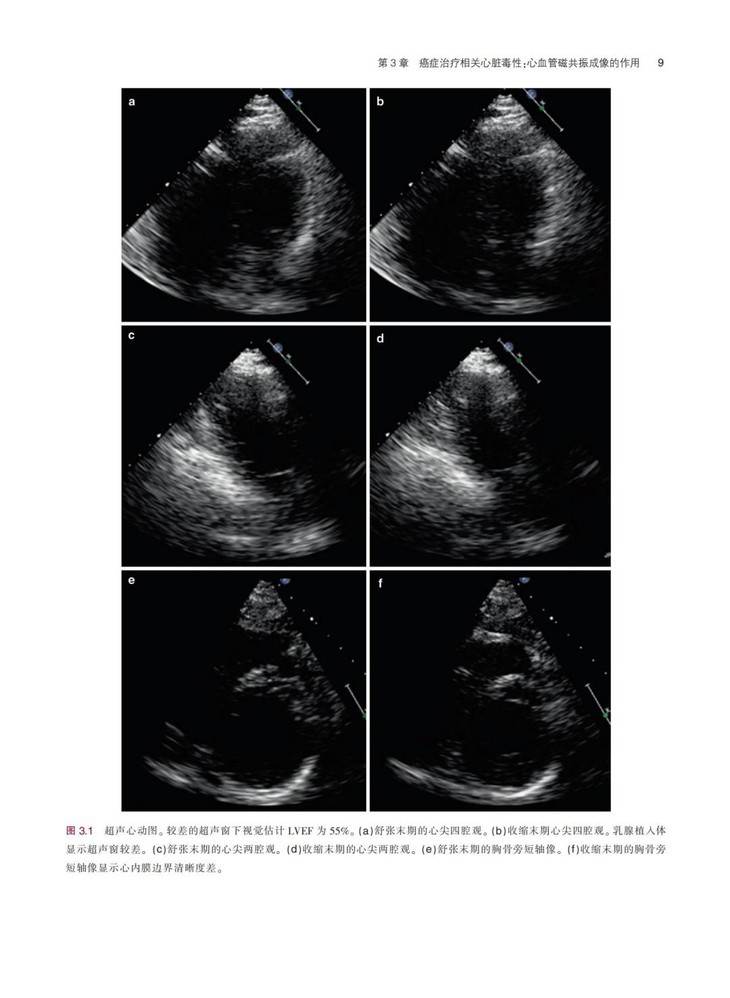

《临床肿瘤心脏病学图解指南》一书结合丰富的临床病例,系统地描述了癌症与心血管领域常见的临床问题,患者主要为既往有心血管疾病的癌症患者,或癌症患者继发复杂心血管疾病,全书对疾病的诊断、检查方式、治疗方式等内容进行了详细阐述,并配有大量的图片,可帮助读者更加清晰地了解相关内容。本书通过结合相关临床病例的方式,在强化理论的同时,突出临床应用特性。本书对我国临床肿瘤心脏病学的基础研究和临床实践有明确的指导意义,对于肿瘤或心血管领域的临床医师及相关研究者具有很强的参考价值。

配有大量手术图片和超声图片,图文并茂,可以为读者提供临床指导,实用性很强